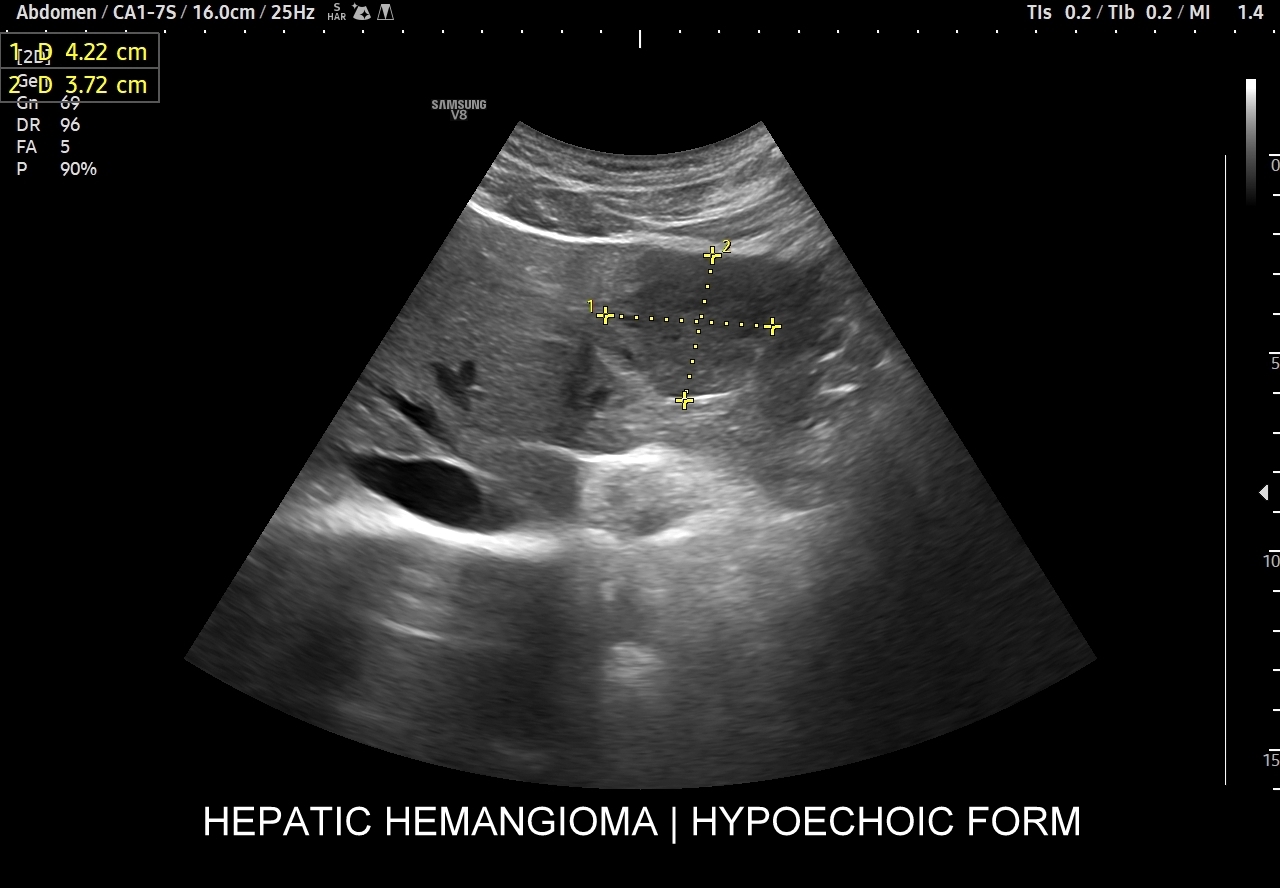

Naczyniaki duże, tj. powyżej 2-3 cm, mogą mieć strukturę niejednorodną echogenicznie, w tym obszary hypoechogenne. Spotyka się także naczyniaki o charakterystyce normo- lub hypechogenicznej, w szczególności w wątrobie stłuszczonej. Z powyższych względów należy mieć na uwadze i zapamiętać, że badanie USG w podstawowym trybie B nie jest wystarczające do postawienia rozpoznania naczyniaka wątroby. W ramach obrazowej diagnostyki różnicowej najbardziej pomocnym jest badanie USG z kontrastem (CEUS), w którym to naczyniak wątroby posiada charakterystyczny wzorzec wypełnienia.

Podsumowanie. Najczęstszą formą sonograficzną łagodnego naczyniaka wątroby jest ognisko hyperechogenne, ale podobną formę przyjmuje również wiele złośliwych zmian metastatycznych. Naczyniak wątroby może przyjmować także formę zmiany niejednorodnej echogenicznie, jak i hypoechogennej. Podstawowe badanie USG w trybie B nie ma możliwości jednoznacznego rozpoznania naczyniaka. Pierwszorazowo wykryte hyperechogenne zmiany ogniskowe w wątrobie muszą być zawsze zweryfikowane w badaniu uzupełniającym, np. CEUS.